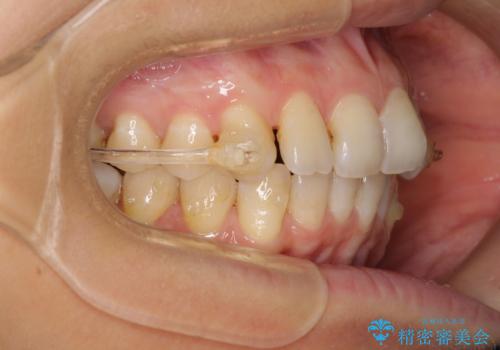

- 前歯の叢生と口元の閉じにくさを気にして来院された患者様です。

奥歯の咬み合わせを見ると、上顎が下顎に対して相対的に前方にありました。

口元の閉じにくさを改善するためには、上顎臼歯を後方に移動させた咬み合わせにする必要があります。

インビザライン単体で改善することも可能ですが、達成する可能性が高くないため、カリエールディスタライザーという補助装置を併用して、より確実性を上げることとしました。

奥歯の咬み合わせを改善しながら、並行してインビザラインで歯列を整えることとしました。